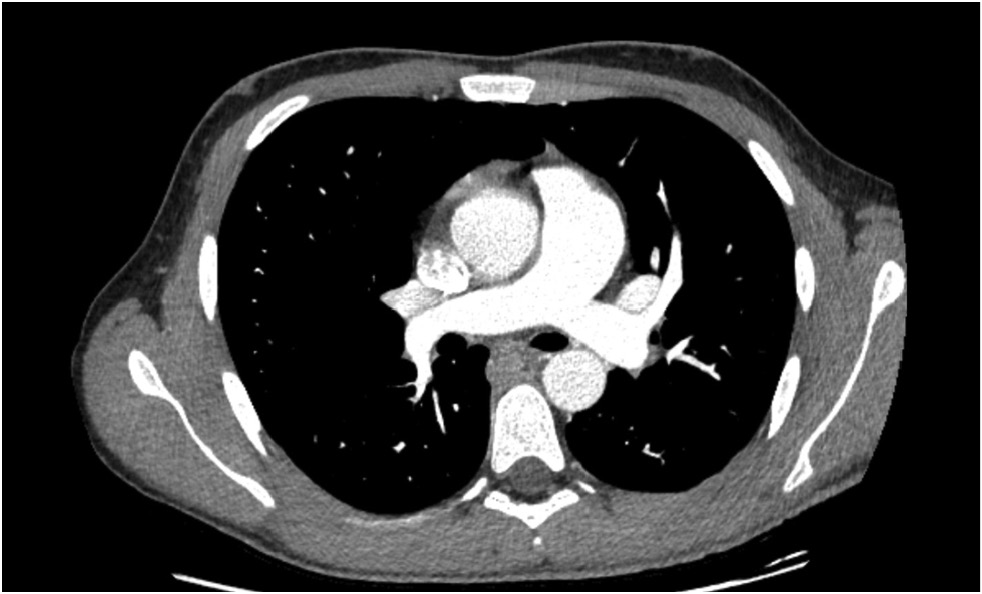

CT pulmonary angiogram showed no abnormal vascular shunts, but confirmed pulmonary trunk dilatation (diameter, 40 mm) (Figure 5), heart chamber dilatation, and myocardial hypertrophy (Figure 6).

Fig. 5. CT pulmonary angiography, axial view. Pulmonary trunk dilatation.

Fig. 6. CT pulmonary angiography, axial view. Myocardial hypertrophy.